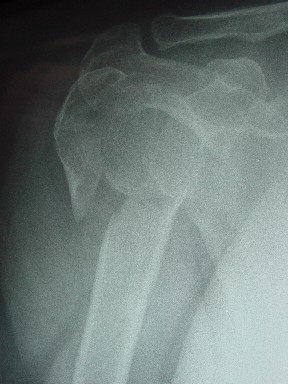

Re: Перелом шейки плеча

|

Уважаемые коллеги

сделать закрытую репозицию с помощью ЭОПа совсем не сложно, после этого еще проще провести 3-6 спиц и получить красивую рентгенограмму. Есть только небольшая проблема это ROTATOR CUFF. Для плечевого сустава только костное восстановление не достаточно. для функции плечевого сустава нужны вращатели.

Давайте представим себе состояние манжетки вращателей после вывиха плеча, а еще и с отрывным переломом бугров. Головка может и прирастет, еесли не будет аваскулярного некроза, но хорошего функционального результата не ждите.

Висеть будет красиво. У людей физически активного периода жизни нужно открыть, восстановить костную анатомию и восстановить сухожильный аппарат.

В этом плане Locking plate очень хороша так как позволяет начать движения сразу после операции.

Клинические снимки - 3 недели после операции

с уважением М. Беренштейн